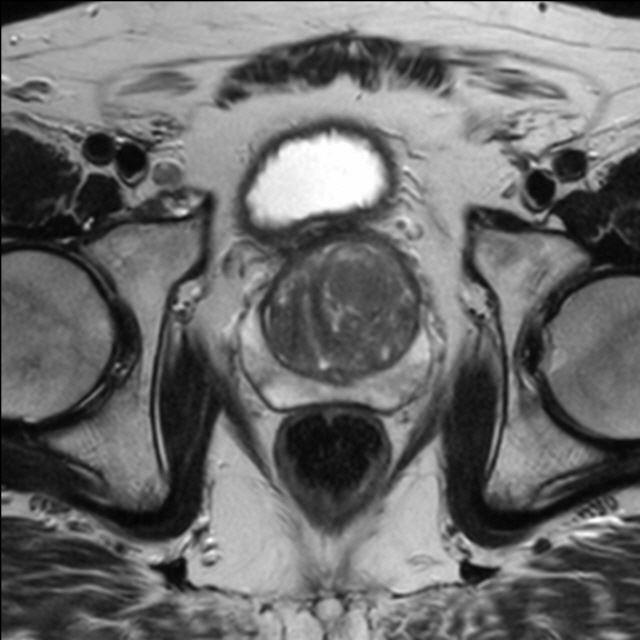

Prostata (mpMRT)

Die multiparametrische MRT der Prostata (mpMRT) bietet eine gute Möglichkeit, mittels bildgebender Diagnostik die Lokalisation, die Ausdehnung und eventuelle Aussaat eines Prostata-Karzinoms darzustellen. Die Untersuchung dient meist der Abklärung unklarer Tastbefunde, Ultraschallbefunde oder wiederholt erhöhter oder steigender PSA-Werte in der Labordiagnostik.

Die bildgebende Diagnostik der ersten Wahl ist zwar der Ultraschall mit einer Spezialsonde beim Urologen und ggf. die ultraschallgesteuerte Stanzbiopsie verdächtiger Befunde. Bei fehlender Darstellung des Tumors im Ultraschall oder vergeblichen Biopsien kann aber die MRT als Problemlöser eingesetzt werden: Sie zeigt dem Urologen, wo eine weitere Biopsie die Diagnose sichern kann. Außerdem kann die MRT bei ausgedehnten Tumoren einen Überblick über die Beteiligung der Nachbarorgane verschaffen und Absiedlungen (Metastasen) entdecken.